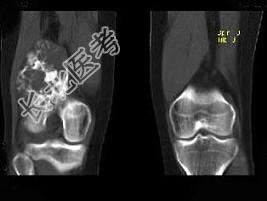

- 单项选择题男,34岁, 大腿下段疼痛2年,可摸到肿块, 结合图像,最可能的诊断是 ( )

A、骨肉瘤

B、软骨肉瘤

C、软骨瘤

D、纤维肉瘤

E、巨细胞瘤